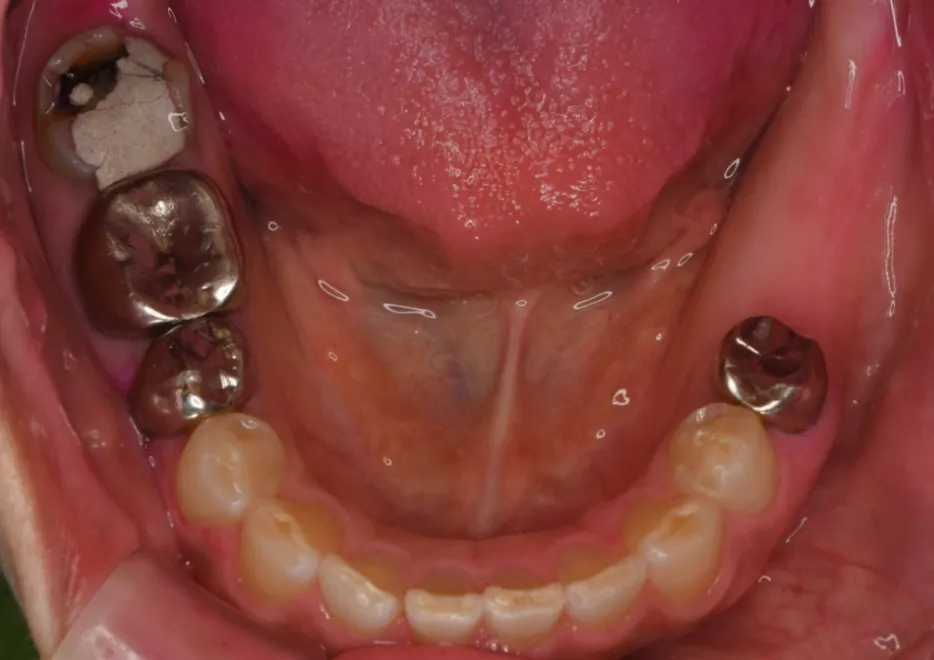

インプラント治療の症例

治療前

治療後

| 治療名称・年齢 | 左下臼歯2本のインプラント 58歳 |

|---|---|

| 総額 治療費用 | 84万円 |

| 費用の詳細 | インプラント1本42万円 |

| 総治療期間 | 2か月 |

| 通院頻度 | 2週間に1度 |

| 症状 | 左下に歯が無くて食事しにくく、右でばかり咬んでしまう。 |

| 治療方法 | ①左下の奥歯が欠損している箇所に、2本インプラントを埋入します。 ②2か月後インプラントと下顎骨が生着したところで、かぶせの型どりをします。 ③インプラントとセラミックのかぶせをスクリューで固定して治療を終了します。 |

| 治療結果 | 今まで、左下の奥歯が欠損していて咬めなかったが、左側で固い物も咀嚼できることが可能になったと、確認しています。咬む力が前後左右に分散するために、インプラント以外の歯が咬耗、破折するリスクが低くなりました。 |

| リスク/副作用 | 出血、神経損傷などのリスクがあるため、CT撮影による診断や、サージカルガイドの使用などによって、リスクを回避することが必要です。 |